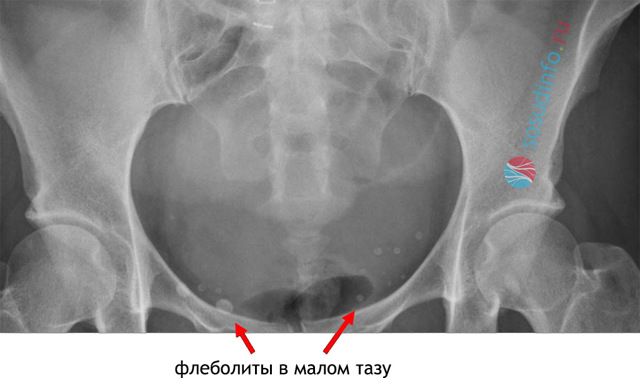

Флеболит это небольшие частички закальцинированных тромбов, которые образовываются в венах. На рентгеновских снимках проявляются в виде белых пятен.

Часто возникают в области таза, почках. Также они обнаруживаются в челюстно-лицевых отделах, и при варикозных расширениях.

- Рентген. Снимок позволяет определить точную локализацию камней. Они имеют овальную форму, характерную концентрацию.

Кальциевые камни органов или вен малого таза наиболее часто обнаруживаются случайно на рентген-снимках в виде мелких камнеобразных уплотнений. Для определения точной локализации, а также размера образований проводят магнитно-резонансную или компьютерную томографию, позволяющую оценить их особенности в различных проекциях.

- Рентгенография определяет флеболиты в проекции малого таза в виде округлых теней с множеством слоев. Важным диагностическим признаком является наличие радиопрозрачного центра (симптом «хвоста кометы»).

- Рентгенография малого таза. На обзорных снимках рентгеноконтрастные флеболиты видны как овальные структуры с концентрическими кольцами («расслоениями»). Важными диагностическими признаками тазовых камней принято считать наличие радиопрозрачного центра, симптом «хвоста кометы».